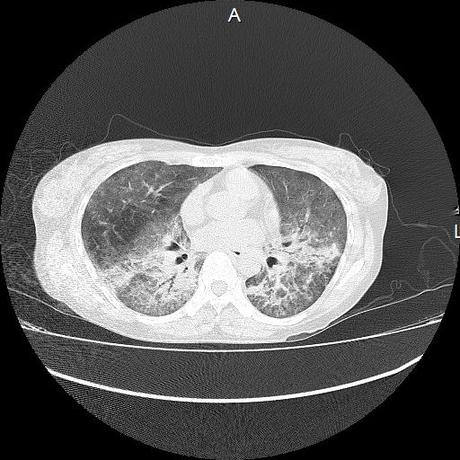

El parénquima pulmonar con areas parcheadas difusas en vidrio despulido combinadas con otras areas hipodensas de baja atenuación debidas a atrapamiento aéreo y engrosamiento intersticial y zonas de fibrosis de predominio en lóbulos medios e inferiores de ambos pulmones.

- LOS HALLAZGOS PUEDEN ESTAR EN RELACIÓN A NEUMOPATIA INTERSTICIAL PROBABLE ETIOLOGIA HIPERSENSITIVA VS AUTOINMUNE/BACTERIANA/FUNGICA.